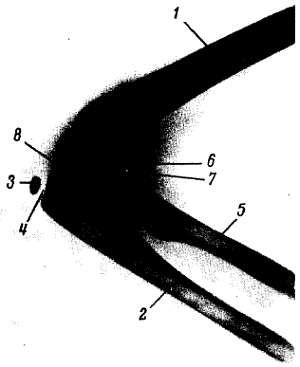

Рис. 44.Рентгенограмма локтевого сустава девочки 9 лет; боковая проекция.

1 - плечевая кость; 2 - локтевая кость; 3 - эпифиз локтевой кости; 4 - эпифизарный хрящ; 5 - лучевая кость; 6 - эпифиз лучевой кости; 7 - эпифизарный хрящ; 8 - суставная щель.